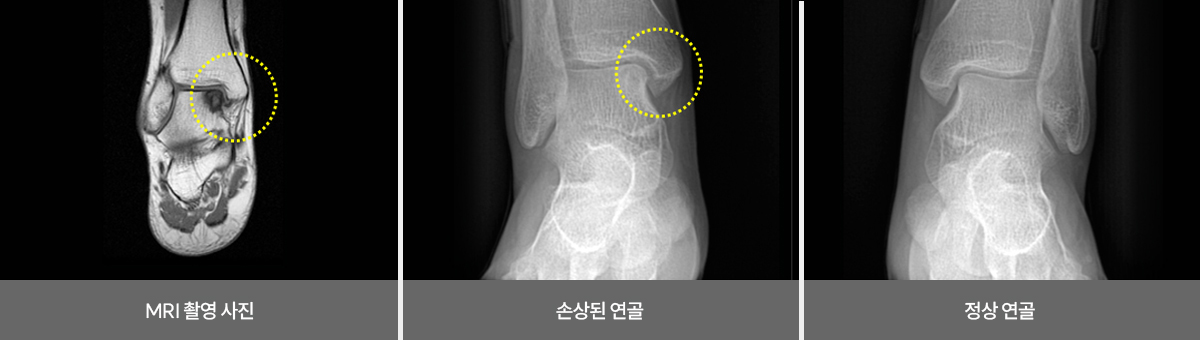

발목 연골 손상

발목 인대가 손상 되었을 때 치료를 하지 않고 그대로 방치하여 회복 되지 않거나

갑작스러운 외부의 충격으로 인해 연골 손상이 발생하며, 손상된 연골은 자연적인 재생이 불가능하여

반드시 재생 치료를 진행 해야 관절염으로 진행 되는 것을 예방 할 수 있습니다.

비수술 치료 : 약물, 고정치료 (깁스 또는 보조기), 물리치료, 주사치료, 도수치료

수술치료 : 발목 연골재생치료